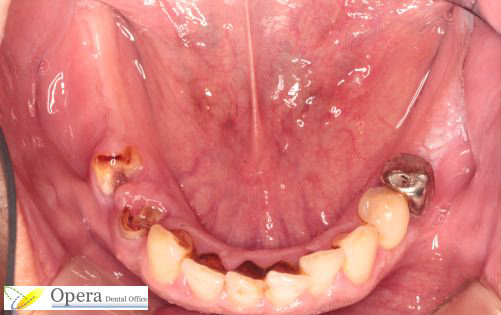

初診時です。

虫歯でボロボロの歯はさずがに残せません。

また、左下(向かって右)の奥歯部分の粘膜はインプラントには適しておらず、医療センターで切除していただきました。